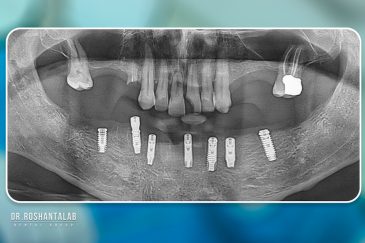

کلینیک تخصصی دکتر حسن روشن طلب با همکاری جمعی از متخصص ایمپلنت دندان و جراح فک و صورت بنام در حال فعالیت می باشد. این مجموعه مأموریت خود را ارائه خدمات تکمیلی دندانپزشکی در زمینه درمان های تخصصی و عمومی به شرح ذیل انجام می شود.

🔸 کاشت ایمپلنت دندان بدون درد

🔸کاشت ایمپلنت فلپ لس یا بدون جراحی و بدون بخیه زیر سه دقیقه

🔸 کاشت دندان یک روزه ( کشیدن و کاشت همزمان )

🔸 ایمپلنت دیجیتال و ساخت روکش دیجیتال

🔸جراحی پیشرفته نظیر سینوس لیفت

🔸ایمپلنت دندان با بیهوشی

تجربه کاشت دندان دیجیتال و بدون درد در ۳ دقیقه! استفاده از برترین برندها زیر نظر جراح، با هزینه مناسب و خدمات کامل از کاشت دندان تا روکشارتودنسی دندان

انتخاب بهترین متخصص ایمپلنت که به تکنیکهای روز دنیا مسلط باشد، تضمینکننده سلامت فک و زیبایی لبخند شماست. در کلینیک دندانپزشکی دکتر روشنطلب، ما با بهرهگیری از تجهیزات دیجیتال در ۵ شعبه فعال (تهران، اصفهان، رشت و استانبول ترکیه)، خدمات تخصصی کاشت ایمپلنت دندان را برای بیمارانی که کیفیت و دقت برایشان اولویت دارد، ارائه میدهیم. در این متد، پروسه درمان با ظرافت بالا انجام شده؛ راهکاری ایدهآل برای کسانی که به دنبال درمان بدون درد با بالاترین نرخ موفقیت هستند.